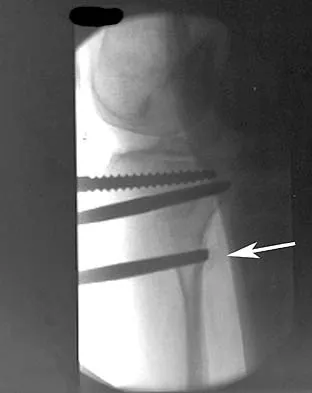

A patient with rheumatoid arthritis with both ankle and subtalar involvement was treated as shown in Figures 11a and 11b. What complication is unique to this type of fixation?

Explanation

The interlocking screws at the proximal end of the rod can act as a stress riser and lead to fracture. Postoperative pain at this level should prompt inclusion of this diagnosis in the differential. Removing the screws following bone union can decrease the chances of this occurring. A short rod that avoids the diaphyseal area may also be beneficial. Rotatory deformity is controlled by the perpendicularly oriented distal transfixion screws. Talar osteonecrosis would be unusual since the dissection can be minimized with an intramedullary rod. Any type of hardware can fail if the construct does not lead to a solid arthrodesis. Nunley JA, Pfeffer GB, Sanders RW, et al (eds): Advanced Reconstruction: Foot and Ankle. Rosemont, IL, American Academy of Orthopaedic Surgeons, 2004, pp 236-237. Thordarson DB, Chang D: Stress fractures and tibial cortical hypertrophy after tibiotalocalcaneal arthrodesis with an intramedullary nail. Foot Ankle Int 1999;20:497-500.

- Hammett R, Hepple S, Forster B, et al: Tibiotalocalcaneal (hindfoot) arthrodesis by retrograde intramedullary nailing using a curved locking nail: The results of 52 procedures. Foot Ankle Int 2005;26:810-815.